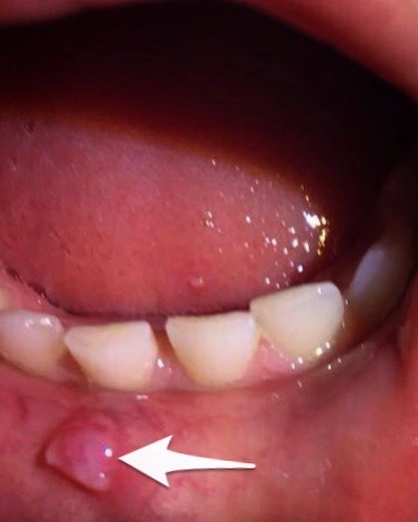

ТАКОЕ увидеть во рту своего ребёнка.

Хотя страшного конкретно тут ничего нет.

Не поверите, ЭТО образование - следствие неправильного прикуса ребёнка.

Называется - хроническая травма.

Вот и доприкусывался, что такое вот великолепие образовалось.

А причина травмы - условия, созданные неправильным прикусом